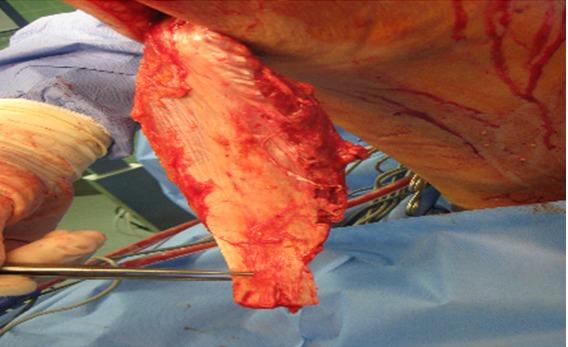

With the increase of endoprosthetic knee replacements, there is also an increase of critical wounds to the knee due to a high incidence of soft tissue problems (ranging from wound healing defects to severe wound infections). The literature describes a general rate of soft tissue complications of up to 20% [1], [2], with 5% [3] involving exposed bone. These complications are an increasingly important problem for surgeons. Since sufficient coverage of bones, tendons and prosthetic material with soft tissue is a necessity, the use of a pediculated muscle flap is the only solution in some cases. The gastrocnemius muscle is very useful for this purpose. It is an elaborate procedure which is associated with a high rate of complications. However, this procedure can establish a secure coverage with soft tissue, and the function of the prosthesis and the patient's extremity can be saved. We have treated 23 patients with a gastrocnemius rotation flap after knee prosthesis or knee arthrodesis infection with consecutive soft tissue damage at our hospital from 8/2004 through 3/2011. The overall rate of healing of the knee infections with stable soft tissue status is almost 87%. The revision rate with lifting of the flap and revision of the sutures at the point of insertion as well as the point of extraction was about 35% with long-term conservative or additional surgical treatments.

随着人工膝关节置换手术数量的增加,由于软组织问题(从伤口愈合缺陷到严重伤口感染)的高发生率,膝关节的严重伤口也在增多。文献报道软组织并发症的总体发生率高达20%[1,2],其中5%[3]涉及骨外露。这些并发症对外科医生来说是一个日益重要的问题。由于需要用软组织充分覆盖骨骼、肌腱和假体材料,在某些情况下,使用带蒂肌瓣是唯一的解决办法。腓肠肌在这方面非常有用。这是一个复杂的手术,并发症发生率很高。然而,该手术可以用软组织建立可靠的覆盖,从而挽救假体和患者肢体的功能。2004年8月至2011年3月期间,我们医院对23例膝关节假体或膝关节融合术后感染并伴有连续性软组织损伤的患者采用了腓肠肌旋转瓣进行治疗。膝关节感染且软组织状况稳定的总体愈合率约为87%。通过长期保守治疗或额外的手术治疗,瓣掀起及瓣插入点和抽出点缝线修复的翻修率约为35%。